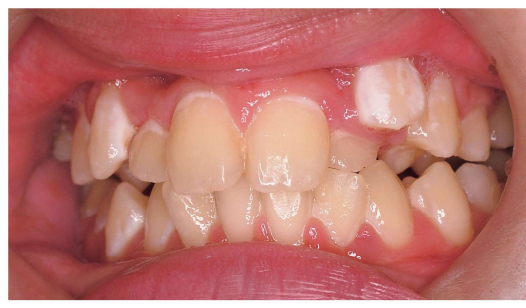

9 歳の女児。前歯の歯並びが悪いことを主訴として来院した。初診時の口腔内写真(別冊No. 18A)とエックス線画像(別冊No. 18B)を別に示す。

第一期治療として適切なのはどれか。 1 つ選べ。

a 右上C の抜歯

b 左上C の抜歯

c  左上4 の抜歯

d  上顎両側2 の補綴処置

e 上顎右側臼歯の遠心移動

解答:b

右上3番の先天欠損。なので右上Cは保存。

左上4番はまだ生えていないので抜歯しない。

上顎2番は欠損しているが、補綴処置は小児なのでまだ必要ない。

左上Cがまだ残っており、その下に3番が埋伏しているのがわかる⇒Cを抜いて3を正常な位置に導く。